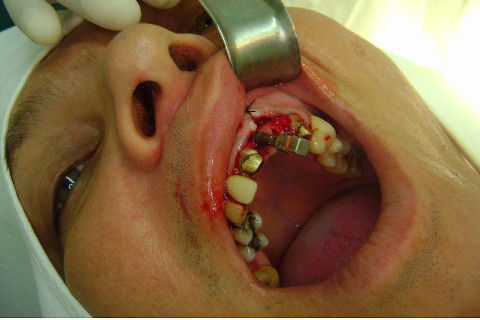

Cirurgia realizada hoje de manhã...No planejamento percebi medindo espessura do rebordo com especímetro que as medidas não estavam muito boas, ou o ideal, em torno de 4,5 a 5 mm ate´o terço médio do rebordo e melhorava no final, com 6 a 7 mm. Optei então por uma pequena expansão usando os expansores rosqueáveis. Aconteceu uma pequena fenestração na hora da fixação dos implantes, especialmente na região do 22 que fraturou o início da tábua óssea, mas não me preocupei porque não foi mais do que 2 mm de fratura em direção apical, o implante ficou infraósseo e com boa estabilidade (60 N no 21 e 40 N no 22). Esta fratura tb não deixou osso completamente solto, foi do tipo galho verde, deixei em posição e suturei normalmente. Só não fiz e nem estava planejado carga imediata mesmo, mais pelo motivo da oclusão inadequada do caso.

Fotos do caso